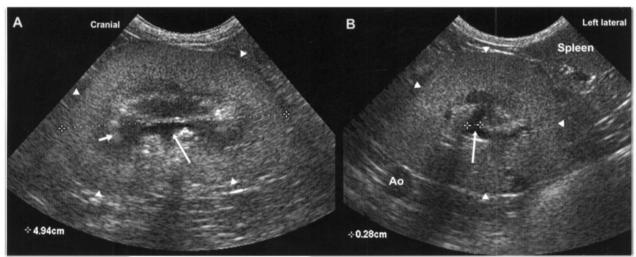

Рис 2. Изображение левой почки (показана треугольниками) собаки мелкой породы при исследовании в продольной (А) и поперечной (В). Почечная лоханка (показана длинной стрелкой) расширена-правильное измерение лоханки.

рис 2.jpgРис 2. Изображение левой почки (показана треугольниками) собаки мелкой породы при исследовании в продольной (А) и поперечной (В). Почечная лоханка (показана длинной стрелкой) расширена-правильное измерение лоханки.